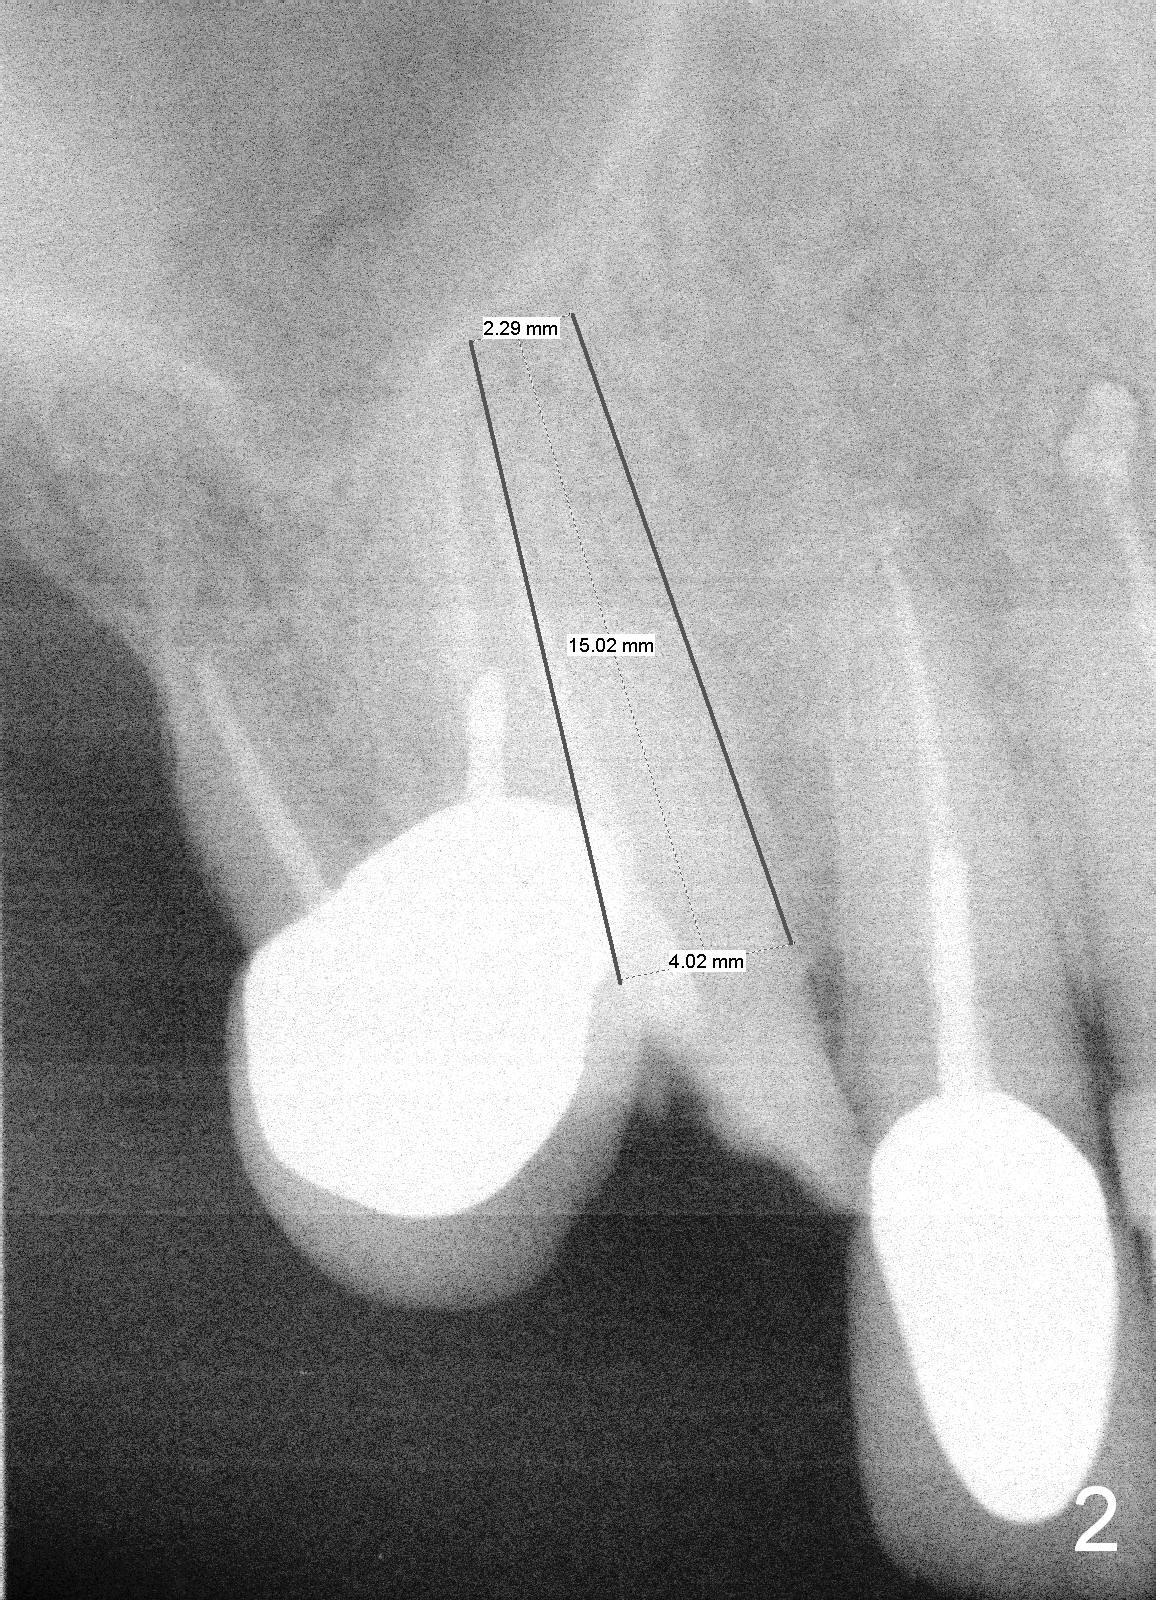

The tooth #6 of a 70-year-old man (TF) fractures subgingival (Fig.1) before final upper left implant restorations. A 15 mm or longer UF implant (Fig.2) seems to be appropriate for the site immediately after extraction (socket treated with Clindamycin).